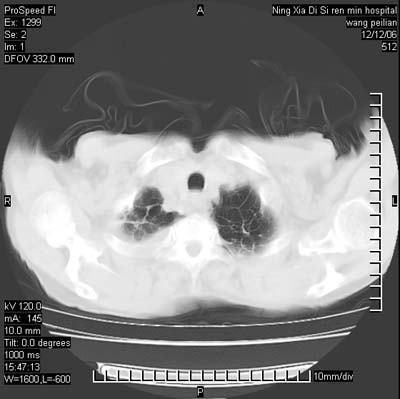

标题: CT5609:胸部:女77 病史不详 [打印本页]

标题: CT5609:胸部:女77 病史不详

两肺可见多个大小不等的结节,左侧有胸水,纵隔淋巴结增大,考虑是细支气管肺泡癌

两肺尖纤维索状影,两下肺结节块状影,且有钙化灶,右胸腔积液。考虑肺结核并胸膜炎。

两肺尖纤维索状影,两下肺结节块状影,且有钙化灶,右胸腔积液。考虑肺结核并胸膜炎肺间质纤维化

考虑:1、慢性支气管炎合并全小叶型肺气肿、间质纤维化;

2、双肺结核;

3、右侧胸膜炎(积液)。

1、双肺继发型肺结核(以纤维、增殖灶为主);

2、右侧胸腔积液;

3、其余符合老年肺改变。

双肺见多个结节状及条索状影,双侧胸腔积液,右侧叶间积液,考虑结核性胸膜炎